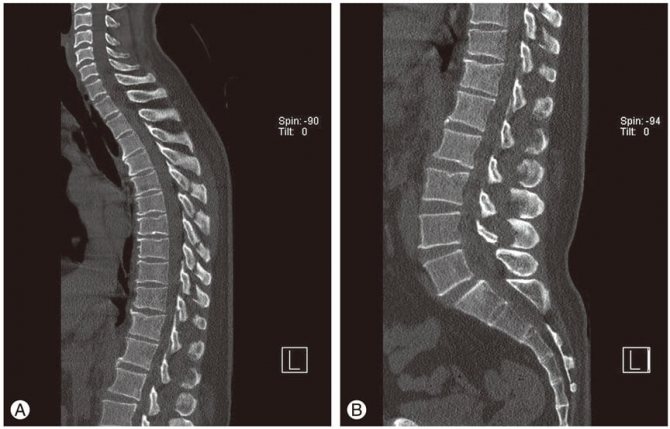

МРТ. Обратите внимание на деформацию позвонков.

- КТ (компьютерная томография) – дает возможность получить трёхмерный снимок проблемной области.

- Магнитно-резонансная томография (МРТ) – дает возможность получить послойный снимок всех тканей и структур области, которая исследуется.

- КТ и МРТ. Эти визуальные методы диагностики считаются при грудном хондрозе наиболее информативными и назначаются для уточнения диагноза. По результатам магнитно–резонансной или компьютерной томографии специалист выявляет место локализации дегенеративно-дистрофического процесса, стадию его развития и степень защемления нервных окончаний.